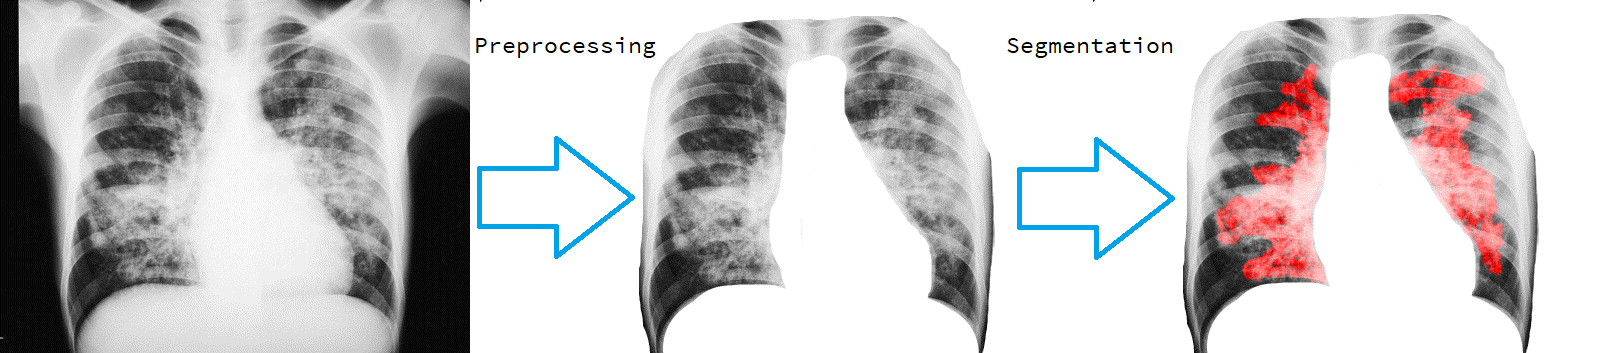

Unets have become the standard method for semantic segmentation of medical images, along with fully convolutional networks (FCN). Unet++ was introduced as a variant of Unet, in order to solve some of the problems facing Unet and FCNs. Unet++ provided networks with an ensemble of variable depth Unets, hence eliminating the need for professionals estimating the best suitable depth for a task. While Unet and all its variants, including Unet++ aimed at providing networks that were able to train well without requiring large quantities of annotated data, none of them attempted to eliminate the need for pixel-wise annotated data altogether. Obtaining such data for each disease to be diagnosed comes at a high cost. Hence such data is scarce. In this paper we use contrastive learning to train Unet++ for semantic segmentation of medical images using medical images from various sources including magnetic resonance imaging (MRI) and computed tomography (CT), without the need for pixel-wise annotations. Here we describe the architecture of the proposed model and the training method used. This is still a work in progress and so we abstain from including results in this paper. The results and the trained model would be made available upon publication or in subsequent versions of this paper on arxiv.